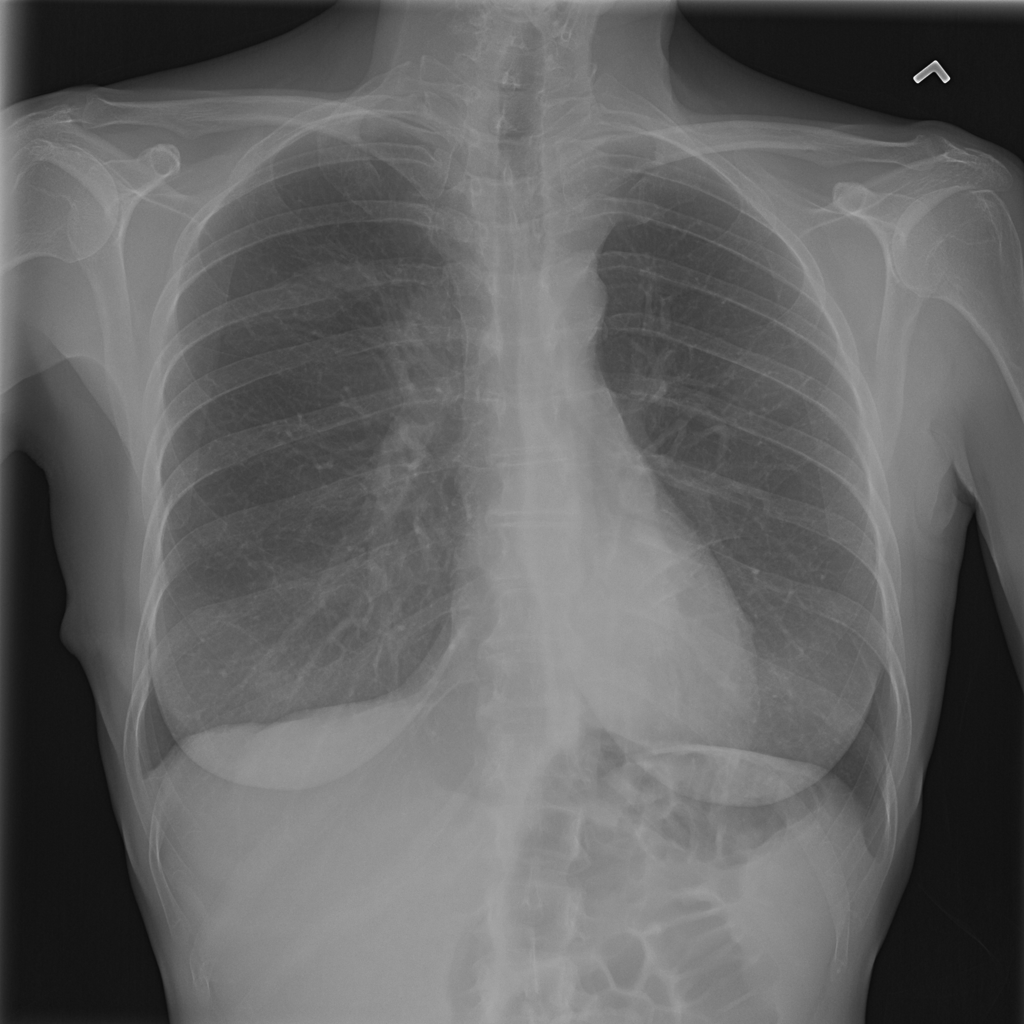

PAT-3938 · IMG-001Nodule

PAT-3938 · IMG-001

AP